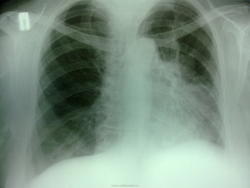

Довольно крупное с четкими контурами, интенсивное образование переднего средостения, не дифференцируется от сердечной тени. Я бы поставила кисту перикарда под вопросом. Остальное зависит от Ваших возможностей - линейная томография, КТ. Что с клиникой и флюороархивом, есть ли данные УЗИ сердца?

Согдасна с Людмилой Григорьевной-образование переднего средостения.

есть архив, к сожалению они не четкие.  12 дней назад в другой поликлинике  поставили заключение- Слева в корне округлой формы с четкими контурами тень 3на4 см интенсивного харакрера. Прозрачность легочного поля снижена за счет гиповентиляции. Сердце без особенностей. Заключение- Заболевание правого легкого.

-достаточный разворот влево, на ПП создается впечатление о гипо- или ателектазе нижней доли слева, но учитывая БП -я думаю о кардиомегалии;

-образований средостения видел мало,и сейчас не вижу, потому думаю о дуге аорты;

аневризма восходящей части аорты-100пудово)) левый корень подтянут кверху похоже и тень с бугристыми контурами над ним- надо исключить (или подтвердить) C-r

Мне видится все несколько иначе: уменьшено левое легкое за счет в/доли, нижняя вздута, органы средостения смещены влево (даже с учетом разворота). У корня на уровне 2-го ребра (на прямом снимке) дополнительное образование. Данные в пользу центрального Са слева с признакками нарушени я бронхиальной проходимости в виде гиповентиляции верхней и вздутия нижней долей. КТ решит вопрос окончательно.

Если даже у опытных коллег разные мнения... Жесть...Страшновато начинать работать )). Снижение прозрачности в/д слева (язычковые сегменты) с некоторым уменьшением в объёме. Диф Ds пневмония слева с нарушением бронхиальной проводимости и гиповентиляцией, объёмный центральный процесс слева. Насчёт тени сердца - честно, затрудняюсь

Вы абсолютно правы!!! Еще раз внимательно посмотрела на снимки-первый с разворотом-в нижнем поле тень сердца, а на боковом левом четко видна тень опухоли с гиповентиляцией S 3. Никогда не торопись!